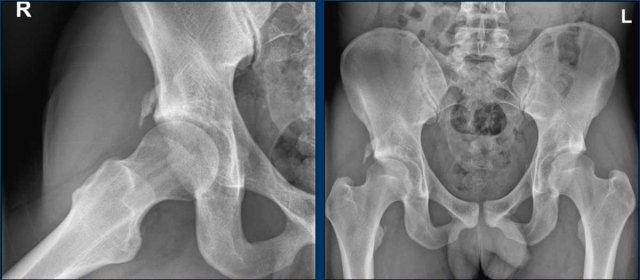

Hình ảnh

Vận động viên thể dục dụng cụ 20 tuổi với các triệu chứng ở hông.

Trên phim chụp AP, vùng đầu-cổ xương đùi trông bình thường.

Trên phim chụp tư thế Dunn, có hình thái Cam ở cả hai bên (mũi tên).